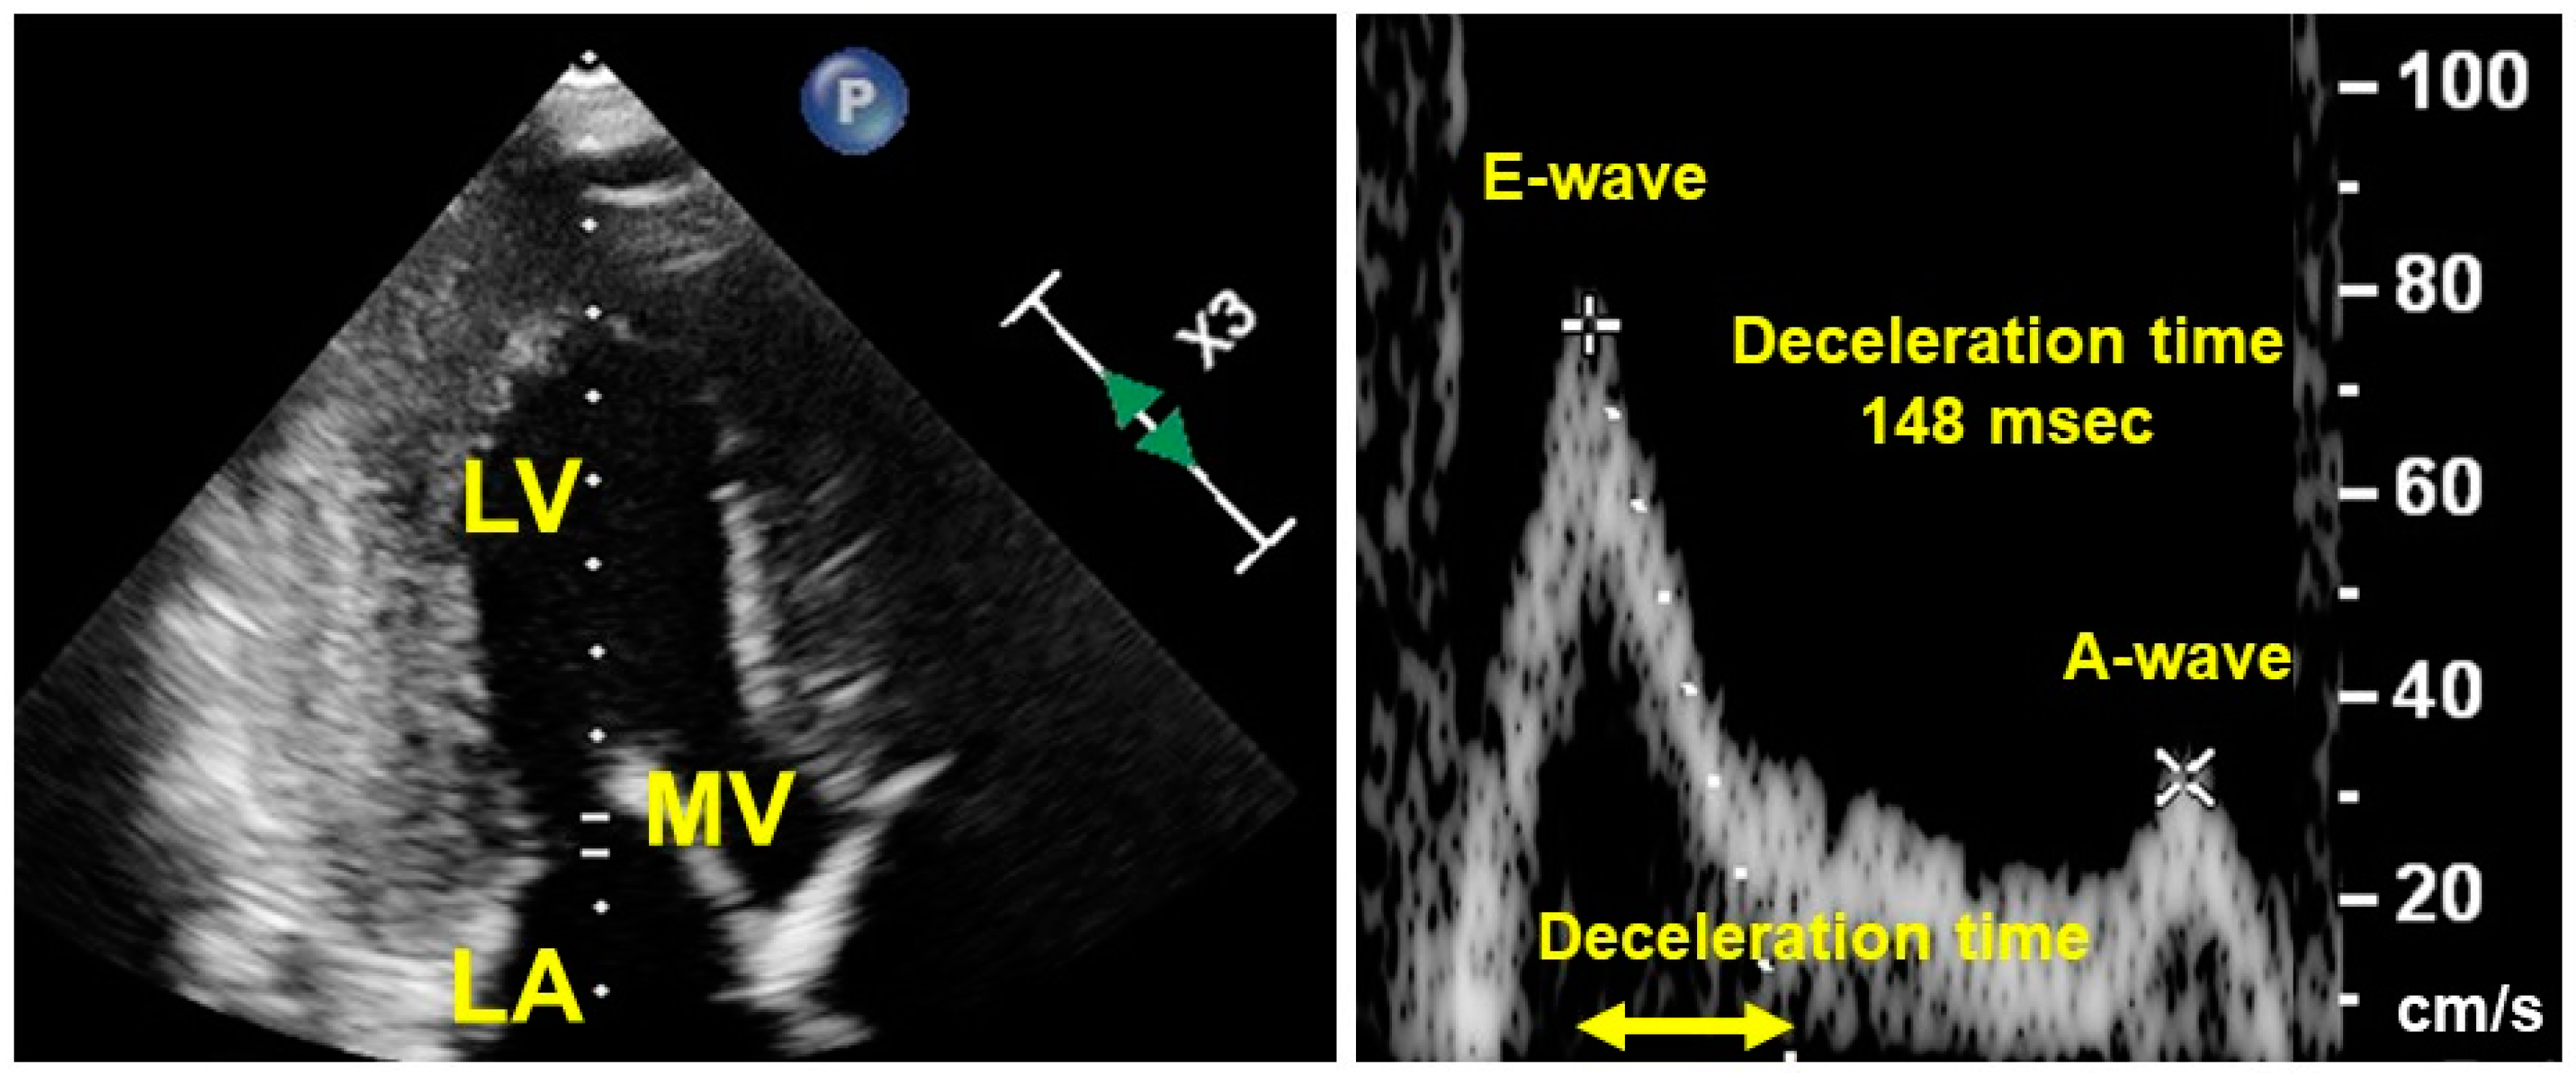

10. Optimal Heart Rate in HFpEF

11. Echocardiography-Guided Heart-Rate Modulation

- Hori, M.; Imamura, T.; Narang, N.; Kinugawa, K. Implications of Doppler Echocardiography-guided Heart Rate Modulation Using Ivabradine. Intern. Med. 2021, 60, 3873–3877. [Google Scholar] [CrossRef]

- Izumida, T.; Imamura, T.; Kinugawa, K. Efficacy of Doppler echocardiography-guided ivabradine therapy. Heart Vessel 2023, 38, 49–55. [Google Scholar] [CrossRef]